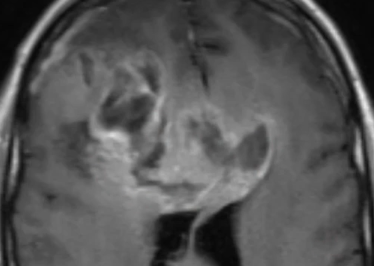

Glioblastome

Decouverte fortuite aux urgences, Confirmé a la patho

Decouverte fortuite aux urgences, Confirmé a la patho